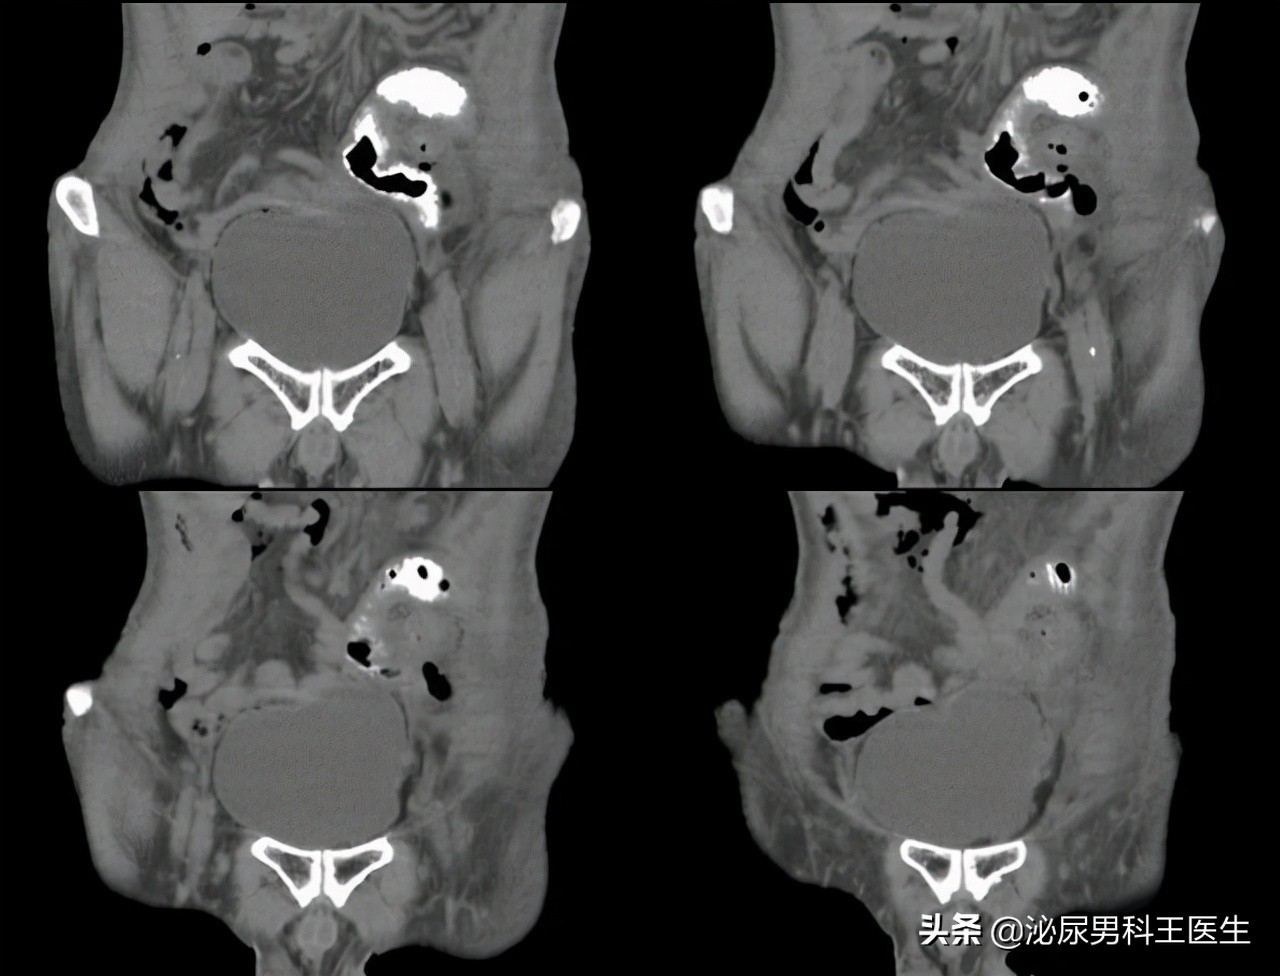

结果在一系列检查后被确诊了III期直肠癌,由于肿瘤目前已经很大且离肛门比较近,想要活命只能是连同肛门一起切除。

比如膀胱癌会根据情况切除患者膀胱,而如果是直肠癌就会切除患者的直肠和肛管,并在患者的腹部开一个小口,将肠管转移到体表而形成的人造切口。

人造切口后可以减轻患者的肠梗阻,保护远端的管道免受损伤,促进患者泌尿系统和肠道疾病的痊愈。 在生活中比较常见的包括回肠造口、尿路造口以及结肠造口等,患者可通过此口完成排尿、排便,这类人群在医学术语上就叫做“造口人”。